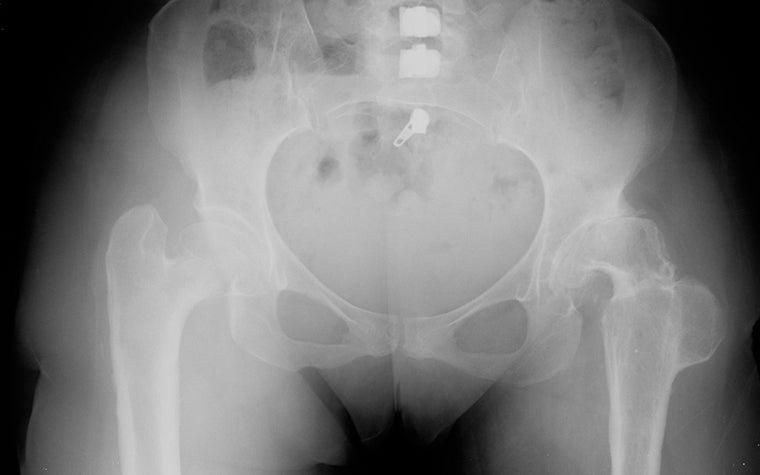

One-click scaling with QuickScale in OrthoView allows the surgeon to choose the appropriate orthopaedic template size and identify the preoperative leg length difference — in this case, 20 mm. They can then select a suitable correction method and test it on screen.

The patient was a female in her late 40s with a long history of DDH. Based on the preoperative X-ray below, it’s evident that she has had previous surgery on her right hip. However, on the left hip, the need for a total hip replacement was identified due to intractable pain.